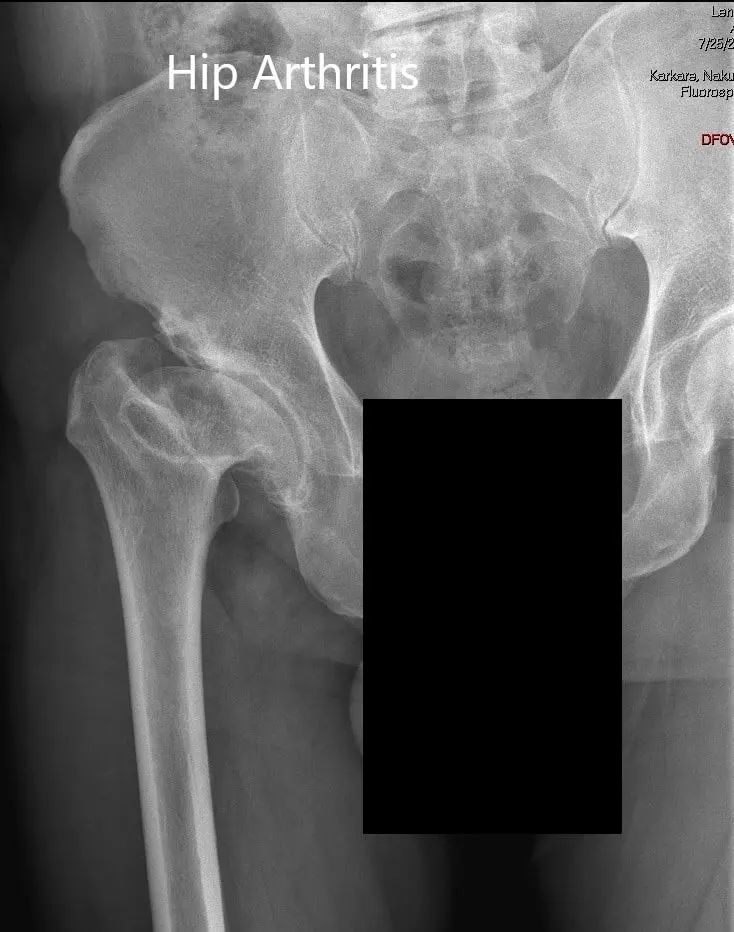

AP and lateral views of the right hip joint

AP and lateral views of the right hip joint - img 2

Imaging revealed markedly deformed right femoral head and impacted the femoral neck. There were severe degenerative changes of the right hip.